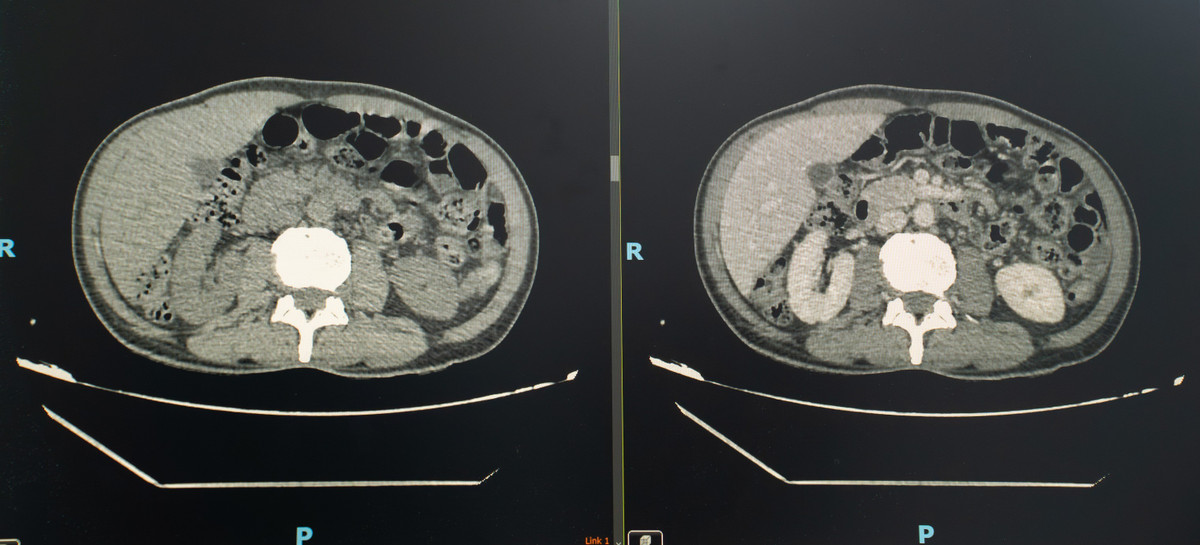

Khi tiến hành siêu âm kỹ hơn, ê-kíp phát hiện một dị vật cản quang xuyên trong nhu mô gan, chiều dài ước tính khoảng 6-7cm. Ngay sau đó, bệnh nhân được chỉ định chụp cắt lớp vi tính (CT scan) ổ bụng.

Kết quả cho thấy có một dị vật dạng que dài nằm hoàn toàn trong nhu mô gan, kèm theo ổ áp xe sâu. Trước nguy cơ biến chứng nặng nếu không điều trị kịp thời, ê-kíp khoa Nội tiêu hóa đã nhanh chóng hội chẩn cùng khoa Ngoại Gan Mật Tụy, thống nhất phương án phẫu thuật lấy dị vật, dẫn lưu ổ áp xe, kết hợp điều trị kháng sinh phù hợp.